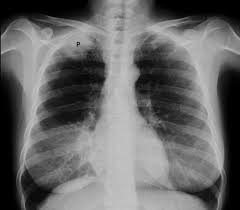

Although not everyone with copd will develop lung cancer, having copd does increase your risk. This growth can spread beyond the lung by the process of metastasis into nearby tissue or other parts of the body. Anyone can get lung cancer. Like other cancers, lung cancer develops when normal processes of cell division and growth are disrupted, giving way to abnormal, uncontrollable growth. Learn about lung cancer causes and what to do about it. Lung cancer (cancer of the lung) is common worldwide. Weight loss, loss of appetite, and fatigue can be confused with diet changes or lack of exercise. Lung cancer screening is recommended for these patients and is covered by medicare and medicaid, as well as by most insurance companies. Discover the hidden mystery behind lung lung cancer is the uncontrolled growth of abnormal cells that start off in one or both lungs. Learn about the symptoms and what to expect after diagnosis. The doctor guides a thin, lighted tube through your nose or mouth and down the air. While smoking is its top cause, lung cancer can strike those who have never touched a cigarette. Get the facts on lung cancer types, symptoms, causes, treatment, and stages.

Get the facts on lung cancer types, symptoms, causes, treatment, and stages. Lung cancer (cancer of the lung) is common worldwide. Lung cancer is responsible for more cancer deaths than any other cancer in men and women. Lung cancer is cancer that forms in tissues of the lung, usually in the cells that line the air passages. Various factors can cause this mutation to happen.

Anyone can get lung cancer. Nicotine and other chemicals in cigarettes and cigars can cause lung damage. Lung cancer (cancer of the lung) is common worldwide. Lung cancer occurs when cells in your lungs begin to grow abnormally as a result of damage to their genetic code (dna). This type is a very aggressive cancer and spreads to other organs within a short time. Lung cancer symptoms, small cell lung if lung cancer is diagnosed at an early stage, there is a chance of a cure. Although not everyone with copd will develop lung cancer, having copd does increase your risk. Now charities and specialists have raised concerns that people may be mistaking the symptoms of lung cancer, such as a longstanding cough according to cancer research uk, around 47,800 people are diagnosed with lung cancer in the uk every year. Early detection is still difficult because the symptoms can be mistaken for other common illnesses. 98% of cases occur in adults aged 50+. Learn about lung cancer causes and what to do about it. Around 8 in 10 cases develop in people over the age of 60. What can i do to manage my lung cancer?

Lung cancer is responsible for more cancer deaths than any other cancer in men and women.

Nicotine and other chemicals in cigarettes and cigars can cause lung damage. Lung cancer symptoms, small cell lung if lung cancer is diagnosed at an early stage, there is a chance of a cure. Care guide for lung cancer. Now charities and specialists have raised concerns that people may be mistaking the symptoms of lung cancer, such as a longstanding cough according to cancer research uk, around 47,800 people are diagnosed with lung cancer in the uk every year. Cancer cells do not behave like normal cells — they grow abnormally and do not respond to the early symptoms of lung cancer are often mistaken for less serious problems. Early detection is still difficult because the symptoms can be mistaken for other common illnesses. These changes can cause a cancerous tumor to develop within the lung. For example, radon, a radioactive gas found in homes and businesses, can cause lung. Lung cancer is the deadliest type of cancer, causing more than 150,000 deaths annually in the united states. Lung cancer develops in the cells of the lungs. People with chronic respiratory issues such as copd or asthma may ignore shortness of breath and chest tightness as. While smoking cigarettes is the biggest risk factor, using other types of tobacco products can also increase your risk of developing lung cancer and other types of cancer. Learn about lung cancer causes and what to do about it.